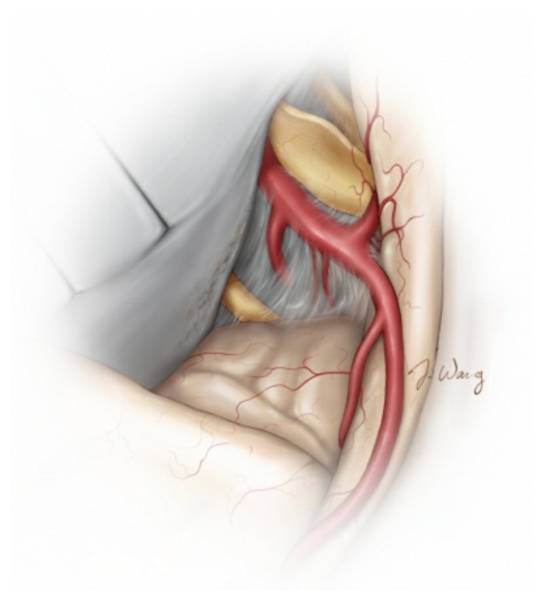

图12. 仔细地将肿瘤前极游离出来,对于识别位于颅底的视神经和ICA是非常重要的(上图)。沿着蝶骨翼内侧走形,可以大致定位视神经管和ICA。在下方的图片中,术中将肿瘤的前额部切除后,吸引器尖端所对的就是视神经和颈内动脉的位置。电凝后残留的肿瘤组织位于天幕边缘。

图13. 小心松动内侧的包膜,锐性分离可以游离出视神经和近端ICA。切开镰状韧带以松解视神经。可见后交通动脉起源自ICA后壁。该血管可用于指示动眼神经。如果肿瘤与神经或血管粘连紧密,需避免过度的操作和钝性分离,留下一薄层肿瘤组织。即便轻柔地处理动眼神经和天幕周围的肿瘤组织,大多数患者术后仍会出现一过性动眼神经和滑车神经麻痹。应尽量避免在这些血管周围电凝天幕。

图14. 接下来,笔者会将肿瘤后方的包膜与颞叶分开。肿瘤位于中颅底前方的基底已经被离断。需要注意相关的重要神经血管结构,主要是后交通动脉、脉络膜前动脉和动眼神经,受到肿瘤推移后,这些结构很可能出现在无法预料的位置,导致术者判断错误,笔者宁可在探查时不放过每一个可疑的结构,也不愿造成无可挽回的损伤后追悔莫及。在处理出血时,过度的电凝对保留周围的神经血管有害的。肿瘤内侧有蛛网膜覆盖在基底池和脑干表面,予保持完整。

图15. 保留肿瘤包膜周边的蛛网膜平面非常重要。为避免脑梗死的发生,笔者会保留每一根穿支动脉,减少对它们的操作。在全切肿瘤后,蝶骨翼内侧受侵犯的硬脑膜,笔者会电凝烧灼。图示为切除肿瘤后的神经血管解剖结构。